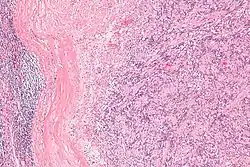

| Micrograph of an intranodal palisaded myofibroblastoma. H&E stain. | |

IPMs are diagnosed by examination of the tissue by a pathologist. They have a rim of peripheral lymphoid tissue (remnant of a lymph node) and consist of spindle cells with nuclear palisading. Red blood cell extravasation is common and blood vessels surrounded by collagen with (fine) peripheral spokes (amianthoid fibers) are usually seen.[2]

Immunostains for smooth muscle actin and cyclin D1 are characteristically positive. The main histologic differential diagnosis is schwannoma.

High mag.